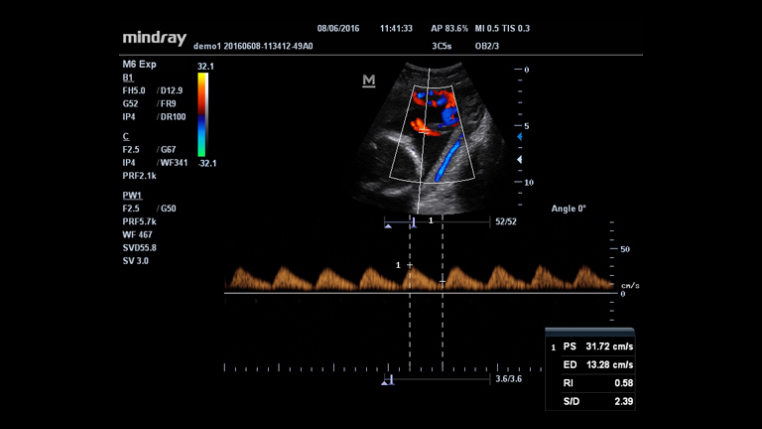

An innovative technology to better visualize tiny vessels and complex flow patterns, based on Mindray's exclusive processing algorithm.

Auto measurement of fetal parameters:trace and calculate the BPD,OFD,HC,AC and FL on a single click.

Smart Track

MindrayŌĆÖs unique function: Continuously track the color flow and optimize the best Color box position and angle in real time scanning